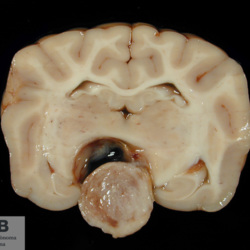

Pàgina anterior de 637 Pàgina següent 3181 total Canine Specie: Canine Organ: Nerve Lesion: - Lesion modifier: - Disease: - Files/Expedient: N-214/09 Not viewed Canine Specie: Canine Organ: Brain Lesion: Hemorrhage Lesion modifier: - Disease: - Files/Expedient: N-190/09 Not viewed Feline Specie: Feline Organ: Lung Lesion: Atelectasis Lesion modifier: - Disease: - Files/Expedient: N-167/09 Position: 136 (2 views) Canine Specie: Canine Organ: Pituitary gland Lesion: Carcinoma Lesion modifier: Carcinoma - Adenocarcinoma Disease: - Files/Expedient: N-113/09 Not viewed Canine Specie: Canine Organ: Pituitary gland Lesion: Carcinoma Lesion modifier: Carcinoma - Adenocarcinoma Disease: - Files/Expedient: N-113/09 Not viewed Pàgina anterior de 637 Pàgina següent Títol Select...Avian (Exotic) (110)Avian (Poultry) (76)Bovine (317)Canine (935)Caprine (47)Equine (257)Feline (326)Ferret (19)General (127)Marine mammal (22)Non-human primate (20)Ovine (328)Porcine (379)Rabbit (61)Reptile (38)Rodent (28)Wildlife (91) Format Select...- (60)Abomasum (37)Adrenal gland (10)Blood (7)Blood vessel (50)Body as a whole (19)Bone (57)Bone marrow (21)Brain (93)Cloaca (1)Diaphragm (2)Ear (5)Esophagus (39)Eye (16)Fetus (12)Gallbladder (23)Gizzard (2)Heart (265)Intestine (356)Joint (32)Kidney (443)Larynx (5)Liver (326)Lung (264)Lymph node (91)Mammary gland (10)Mediastinum (1)Muscle (22)Nasal cavity (22)Nerve (7)Omasum (5)Oral cavity (63)Ovary (14)Oviduct (8)Pancreas (7)Parathyroid (5)Penis (10)Peritoneum (65)Pharynx (9)Pituitary gland (6)Placenta (7)Prostate (8)Proventriculus (3)Reticulum (1)Rumen (28)Sinus (7)Skin (181)Spinal cord (15)Spleen (105)Stomach (125)Teeth (1)Testicle (11)Thoracic cavity (31)Thymus (13)Thyroid gland (5)Tongue (32)Tonsils (11)Trachea (11)Urethra (5)Urinay bladder (61)Uterus (27)Vagina (1)Vulva (1)Yolk sac (1) Cobertura Select...- (152)Abomasitis (26)Abscess (27)Acidosis (1)Adenocarcinoma (20)Adenoma (9)Aerosacculitis (6)Agenesis (1)Agnathia (1)Alopecia (7)Amyloidosis (12)Aneurysm (6)Angiectasis (1)Anthracosis (1)Arteritis (11)Arthritis (15)Arthrogryposis (6)Artifact (4)Ascites (13)Atelectasis (8)Atherosclerosis (5)Atresia (1)Atrial septal defect (2)Atrophy (10)Autolysis (7)Bronchitis (6)Bronchopneumonia (26)Cachexia (2)Carcinoma (103)Cardiomyopathy (19)Cellulitis (2)Chemodectoma (4)Cholangiohepatitis (4)Cholangitis (19)Cholecystitis (4)Cholestasis (5)Chondrodysplasia (2)Chondrosarcoma (2)Chronic passive congestion (13)Chylothorax (2)Cirrhosis (6)Coelomitis (3)Coenurus cerebralis (4)Colitis (40)Congestion (17)Conjunctivitis (5)Coronitis (3)Cryptorchidism (3)Cyst (25)Cystitis (24)Dermatitis (69)Diaphragmatic hernia (4)Dilation (28)Discospondylitis (1)Disseminated intravascular coagulation (7)Dyschondroplasia (1)Dysplasia (29)Ectopia cordis (1)Ectopic ureter (1)Edema (55)Emphysema (5)Encephalitis (5)Endocardiosis (14)Endocarditis (26)Endometritis (5)Enteritis (118)Enterolith (6)Epulis (3)Esophagitis (14)Fasciitis (1)Fibrosis (7)Fibrous osteodystrophy (8)Fistula (1)Folliculitis (3)Fracture (2)Gastritis (34)Gingivitis (5)Glioma (8)Glomerulonephritis (21)Glossitis (25)Glycogenosis (1)Gout (8)Granuloma (2)Granulosa cell tumor (4)Hemangioma (9)Hemangiosarcoma (46)Hematoma (8)Hemoglobinuria (2)Hemopericardium (12)Hemoperitoneum (2)Hemorrhage (100)Hemosiderosis (7)Hemothorax (2)Hepatitis (78)Hernia (11)Histiocytosis (3)Hydatid cyst (11)Hydrocephalus (9)Hydrometra (1)Hydronephrosis (22)Hydropericardium (6)Hydrothorax (3)Hydroureter (5)Hyperkeratosis (8)Hyperostosis (4)Hyperplasia (37)Hypertrophy (9)Hypopigmentation (1)Hypoplasia (7)Hypopyon (1)Impaction (6)Infarction (63)Insulinoma (6)Intussusception (5)Jaundice (17)Laminitis (2)Laryngitis (2)Leiomyoma (5)Leukemia (13)Lipidosis (36)Lipoma (7)Lymphadenitis (45)Lymphadenopathy (7)Lymphangiectasia (6)Lymphangitis (5)Lymphoma (221)Malacia (11)Malignant melanoma (15)Mast cell tumor (11)Mastitis (8)Megaesophagus (2)Melanosis (3)Melena (4)Meningioma (6)Meningitis (6)Meningocele (2)Meningoencephalitis (5)Mesothelioma (5)Methemoglobinemia (2)Mineralization (10)Mucocele (5)Mucometra (1)Multilobular bone tumor (1)Mummification (3)Myelofibrosis (1)Myocarditis (4)Myositis (5)Necrosis (81)Nephritis (113)Nephroblastoma (6)Nephrosclerosis (1)Nephrosis (14)Neuritis (1)Obstruction (13)Omasitis (4)Omphalitis (1)Omphalophlebitis (7)Orchitis (4)Osteoarthrosis (5)Osteomyelitis (9)Otitis (2)Palatoschisis (3)Pancreatitis (3)Panniculitis (3)Papilloma (7)Parakeratosis (14)Patent ductus arteriosus (6)Peliosis hepatis (1)Perforation (17)Pericarditis (35)Peritonitis (39)Persistent right aortic arch (1)Pharyngitis (2)Pheochromocytoma (2)Phlebitis (2)Placentitis (6)Pleuritis (21)Pleuropneumonia (24)Pneumonia (109)Pneumothorax (3)Polycystosis (14)Polyp (5)Polyserositis (6)Posthitis (1)Proctitis (4)Prolapse (3)Prostatitis (3)Proventriculitis (1)Pyelonephritis (24)Pyometra (6)Pyothorax (4)Rhinitis (11)Rumenitis (6)Rupture (24)Salpingitis (3)Sarcoma (57)Sclerosis (1)Scoliosis (2)Seminoma (2)Sequestrum (2)Serous atrophy (14)Sinusitis (7)Splenitis (14)Splenomegaly (9)Spondylitis (6)Spondylosis (1)Stenosis (9)Stomatitis (32)Tenosynovitis (2)Teratoma (3)Thricobezoar (2)Thrombosis (16)Tonsilitis (4)Torsion (13)Tracheitis (4)Tympany (7)Typhlitis (8)Typhlocolitis (4)Ulcer (43)Urethritis (1)Urolithiasis (36)Uroperitoneum (1)Uveitis (1)Vasculitis (15)Ventricular septal defect (3)Volvulus (11) Matèria Select... - (14)- (1653)- (152)Abomasitis - Catarrhal (2)Abomasitis - Catarrhal-hemorrhagic (1)Abomasitis - Chronic (1)Abomasitis - Fibrinous-necrotizing (2)Abomasitis - Hyperplasic (5)Abomasitis - Hyperplasic - Chronic (1)Abomasitis - Necrotic (1)Abomasitis - Necrotizing (2)Abomasitis - Ulcerative (5)Adenocarcinoma (9)Aerosacculitis - Granulomatous (1)Amyloidosis - Chronic (1)Arteritis - Necrotic (2)Arteritis - Necrotizing (1)Arthritis - Chronic (4)Arthritis - Fibrinous-purulent (3)Arthritis - Serous (4)Arthritis - Subacute (1)Ascites - Serous (1)Atrophy - Serous (1)Bronchitis - Catarrhal (3)Bronchitis - Suppurative (1)Bronchopneumonia - Catarrhal-purulent (17)Bronchopneumonia - Fibrinous (1)Bronchopneumonia - Granulomatous (1)Bronchopneumonia - Purulent (1)Bronchopneumonia - Suppurative (5)Carcinoma - Adenocarcinoma (33)Carcinoma - Adenocarcinoma - Hepatocellular (2)Carcinoma - Adenocarcinoma - Mucinous (1)Carcinoma - Basosquamous (1)Carcinoma - Cholangiocellular (3)Carcinoma - Hepatocellular (4)Carcinoma - Metastatic (3)Carcinoma - Squamous cell carcinoma (13)Carcinoma - Transitional cell (2)Cardiomyopathy - Dilated (13)Cardiomyopathy - Hypertrophic (6)Cellulitis - Necrotizing (1)Cholangitis - Chronic (8)Cholangitis - Hyperplasic (3)Cholecystitis - Fibrinous-necrotizing (1)Coelomitis - Fibrinous (1)Coelomitis - Granulomatous (1)Colitis - Catarrhal (3)Colitis - Catarrhal-hemorrhagic (1)Colitis - Fibrinous (1)Colitis - Fibrinous-necrotizing (1)Colitis - Fibrinous-necrotizing (Diphtheritic) (6)Colitis - Granulomatous (2)Colitis - Hemorrhagic (4)Colitis - Hemorrhagic-necrotizing (3)Colitis - Necrotizing (2)Colitis - Ulcerative (6)Congestion - Chronic (2)Conjunctivitis - Hyperplasic (1)Conjunctivitis - Purulent (3)Coronitis - Ulcerative (1)Cystitis - Chronic (3)Cystitis - Fibrinous (1)Cystitis - Fibrinous-necrotizing (1)Cystitis - Follicular (1)Cystitis - Hemorrhagic (6)Cystitis - Hemorrhagic-ulcerative (1)Cystitis - Necrotizing (9)Cystitis - Perforated (1)Dermatitis - Granulomatous (14)Dermatitis - Hyperkeratotic (10)Dermatitis - Hyperplasic (proliferative) (1)Dermatitis - Hyperplastic (10)Dermatitis - Necrotizing (4)Dermatitis - Pustular (4)Dermatitis - Ulcerative (2)Dilation - Chronic (1)Discospondylitis - Necrotizing (1)Dysplasia - Follicular (5)Edema - Interstitial (6)Emphysema - Interstitial (1)Encephalitis - Granulomatous (1)Encephalitis - Nonsuppurative (1)Endocardiosis - Mitral (7)Endocardiosis - Mitral - Chronic (5)Endocarditis - Valvular (6)Endocarditis - Valvular - Mitral (7)Endocarditis - Valvular - Pulmonic (1)Endocarditis - Valvular - Subacute (1)Endocarditis - Valvular - Subaortic (5)Endocarditis - Valvular - Tricuspid (4)Endometritis - Purulent (3)Endometritis - Purulent-hemorrhagic (2)Enteritis - Catarrhal (23)Enteritis - Catarrhal - Acute (1)Enteritis - Catarrhal-hemorrhagic (5)Enteritis - Catarrhal-hemorrhagic - Acute (2)Enteritis - Fibrinous (16)Enteritis - Fibrinous - Acute (3)Enteritis - Fibrinous-necrotizing (7)Enteritis - Granulomatous (14)Enteritis - Granulomatous - Chronic (1)Enteritis - Granulomatous - Multifocal (1)Enteritis - Hemorrhagic (17)Enteritis - Hemorrhagic - Acute (1)Enteritis - Hemorrhagic-necrotizing (1)Enteritis - Hyperplasic (proliferative) (4)Enteritis - Necrotizing (4)Enteritis - Necrotizing - Acute (1)Enteritis - Necrotizing - Hemorrhagic (1)Enteritis - Necrotizing-ulcerative (2)Enteritis - Ulcerative (1)Enteritis - Ulcerative-hemorrhagic (1)Esophagitis - Erosive-ulcerative (6)Esophagitis - Necrotizing (4)Esophagitis - Ulcerative (1)Esophagitis - Ulcerative-necrotizing (1)Fasciitis - Fibrinous-purulent (1)Folliculitis - Purulent (2)Gastritis - Catarrhal (2)Gastritis - Chronic (1)Gastritis - Follicular (1)Gastritis - Hemorrhagic (2)Gastritis - Hemorrhagic-necrotizing (1)Gastritis - Hypertrophic (2)Gastritis - Inclusion bodies (1)Gastritis - Mineralization (1)Gastritis - Mycotic (1)Gastritis - Necrotizing (2)Gastritis - Ulcerative (6)Gastritis - Uremic (3)Gingivitis - Erosive (2)Gingivitis - Hyperplasic (proliferative) (1)Gingivitis - Necrotizing (1)Glomerulonephritis - Chronic (7)Glomerulonephritis - Membranoproliferative (3)Glomerulonephritis - Membranoproliferative - Chronic (1)Glomerulonephritis - Membranous (3)Glomerulonephritis - Membranous - Chronic (1)Glomerulonephritis - Proliferative (2)Glomerulonephritis - Subacute (1)Glossitis - Erosive (2)Glossitis - Granulomatous (6)Glossitis - Hyperplasic (1)Glossitis - Hyperplasic (proliferative) (2)Glossitis - Hyperplastic (1)Glossitis - Necrotizing (2)Glossitis - Necrotizing - Focal (1)Glossitis - Ulcerative (6)Glossitis - Ulcerative - Multifocal (1)Glossitis - Ulcerative - Subacute (1)Glycogenosis (1)Granuloma - Eosinophilic (1)Hemangiosarcoma - Metastatic (2)Hemorrhage - Acute (1)Hemorrhage - Subcapsular (3)Hepatitis - Abscess (9)Hepatitis - Acute (3)Hepatitis - Chronic (4)Hepatitis - Chronic interstitial (6)Hepatitis - Granulomatous (7)Hepatitis - Interstitial - Multifocal (1)Hepatitis - Interstitial - Subacute (1)Hepatitis - Necrotizing (17)Hepatitis - Necrotizing - Acute (2)Hepatitis - Necrotizing - Hemorrhagic (1)Hepatitis - Necrotizing - Subacute (1)Hepatitis - Pyogranulomatous (7)Hepatitis - Subacute (4)Hydronephrosis - Chronic (1)Hydropericardium - Chronic (1)Hyperplasia - Erythroid (1)Hyperplasia - Lymphoid (3)Hyperplasia - Myeloid (1)Hyperplasia - Nodular (8)Hypertrophy - Concentric (2)Hypertrophy - Eccentric (3)Infarction - Acute (17)Infarction - Acute - Multifocal (2)Infarction - Chronic (5)Infarction - Chronic - Multifocal (1)Infarction - Subacute (18)Infarction - Subacute - Focal (2)Laminitis - Chronic (2)Laryngitis - Necrotic (1)Laryngitis - Necrotizing (1)Leukemia - Lymphoid leukemia (2)Leukemia - Non-lymphoid leukemia (6)Lipidosis - Multifocal (1)Lipidosis - Panlobular (1)Lipidosis - Panlobular - Generalized (2)Lymphadenitis - Granulomatous (24)Lymphadenitis - Granulomatous - Chronic (3)Lymphadenitis - Hemorrhagic (1)Lymphadenitis - Necrotizing (5)Lymphadenitis - Necrotizing (caseous) (11)Lymphangitis - Granulomatous (1)Lymphangitis - Purulent (1)Lymphangitis - Ulcerative (1)Lymphoma - Alimentary lymphoma (7)Lymphoma - Cutaneous lymphoma (6)Lymphoma - Lymphosarcoma (2)Lymphoma - Mediastinal lymphoma (1)Lymphoma - Multicentric lymphoma (29)Malignant melanoma - Malignant (1)Malignant melanoma - Metastatic (1)Mast cell tumor - Metastatic (1)Mastitis - Fibrinous-purulent (2)Mastitis - Necrotic (1)Mastitis - Purulent (3)Mastitis - Suppurative (1)Meningitis - Fibrinous-purulent (2)Meningitis - Purulent (4)Meningoencephalitis - Necrotizing (3)Meningoencephalitis - Nonsuppurative (2)Mineralization - Metastatic (4)Myocarditis - Fibrous - Chronic (1)Myocarditis - Granulomatous (1)Myositis - Purulent (2)Necrosis - Acute (1)Necrosis - Cortical (5)Necrosis - Follicular (1)Necrosis - Papillary (8)Necrosis - Papillary - Acute (3)Necrosis - Subacute (3)Necrosis - Tubular (6)Nephritis - Embolic (2)Nephritis - Embolic suppurative (7)Nephritis - Granulomatous (27)Nephritis - Granulomatous - Chronic (1)Nephritis - Granulomatous - Multifocal (1)Nephritis - Interstitial (6)Nephritis - Interstitial - Acute (4)Nephritis - Interstitial - Chronic (41)Nephritis - Interstitial - Subacute (12)Nephritis - Purulent (7)Nephritis - Purulent - Acute (2)Nephritis - Purulent - Multifocal (3)Nephrosis - Cholemic (3)Nephrosis - Hemoglobinuric (10)Omasitis - Fibrinous-necrotizing (1)Omasitis - Hyperkeratotic (1)Omasitis - Necrotizing (2)Omphalophlebitis - Fibrinous-purulent (2)Omphalophlebitis - Purulent (3)Orchitis - Necrotizing (1)Osteomyelitis - Necrotizing (7)Osteomyelitis - Purulent (2)Otitis - Necrotizing (1)Otitis - Proliferative (1)Pancreatitis - Acute (1)Pancreatitis - Chronic (1)Pancreatitis - Granulomatous (1)Panniculitis - Fibrinous-purulent (1)Panniculitis - Necrotic (1)Panniculitis - Parasitic (1)Perforation - Acute (2)Pericarditis - Fibrinous (19)Pericarditis - Fibrinous - Subacute (1)Pericarditis - Fibrinous-necrotizing (1)Pericarditis - Fibrinous-purulent (3)Pericarditis - Fibrous (1)Pericarditis - Fibrous - Chronic (1)Pericarditis - Gangrenous (6)Pericarditis - Granulomatous (1)Pericarditis - Granulomatous - Chronic (2)Peritonitis - Acute (1)Peritonitis - Fibrinous (11)Peritonitis - Fibrinous - Subacute (1)Peritonitis - Fibrinous-purulent (5)Peritonitis - Fibrous (3)Peritonitis - Granulomatous (6)Peritonitis - Purulent (1)Peritonitis - Purulent-hemorrhagic (1)Peritonitis - Pyogranulomatous (3)Pharyngitis - Fibrinous-necrotizing (1)Pharyngitis - Ulcerative (1)Pheochromocytoma - Metastatic (1)Phlebitis - Purulent (1)Placentitis - Fibrinous-necrotizing (1)Placentitis - Necrotic (1)Placentitis - Necrotizing (1)Pleuritis - Chronic (1)Pleuritis - Fibrinous (3)Pleuritis - Fibrinous-purulent (2)Pleuritis - Fibrous (2)Pleuritis - Granulomatous (3)Pleuritis - Hyperplastic (2)Pleuritis - Purulent (2)Pleuritis - Pyogranulomatous (1)Pleuropneumonia - Fibrinous (13)Pleuropneumonia - Fibrinous-necrotizing (5)Pleuropneumonia - Granulomatous (2)Pleuropneumonia - Hemorrhagic-necrotizing (4)Pneumonia - Aspiration (11)Pneumonia - Bronchointerstitial (4)Pneumonia - Bronchointerstitial - Subacute (1)Pneumonia - Embolic (5)Pneumonia - Granulomatous (37)Pneumonia - Granulomatous - Multifocal (4)Pneumonia - Hemorrhagic-necrotizing (2)Pneumonia - Interstitial (7)Pneumonia - Interstitial - Acute (8)Pneumonia - Interstitial - Chronic (6)Pneumonia - Interstitial - Subacute (15)Pneumonia - Necrotizing (2)Pneumonia - Pyogranulomatous (2)Pneumonia - Verminous (5)Polyserositis - Fibrinous (6)Polyserositis - Fibrous (1)Proctitis - Fibrinous-necrotizing (1)Proctitis - Parasitic (2)Prostatitis - Purulent (1)Pyelonephritis - Acute (2)Pyelonephritis - Chronic (3)Rhinitis - Catarrhal (2)Rhinitis - Fibrinous (1)Rhinitis - Granulomatous (4)Rhinitis - Purulent (3)Rumenitis - Acute (1)Rumenitis - Erosive (1)Rumenitis - Necrotizing (1)Rupture - Acute (3)Sarcoma - Fibrosarcoma (12)Sarcoma - Hemangiosarcoma (11)Sarcoma - Histiocytic (7)Sarcoma - Metastatic (1)Sarcoma - Multilobular tumor of bone (1)Sequestrum - Chronic (2)Sinusitis - Suppurative (1)Splenitis - Granulomatous (8)Splenitis - Granulomatous - Chronic (1)Splenitis - Necrotizing (3)Splenitis - Necrotizing (caseous) (2)Spondylitis - Necrotizing (2)Stenosis - Intestinal (1)Stenosis - Valvular - Subaortic (4)Stomatitis - Erosive (12)Stomatitis - Erosive-ulcerative (3)Stomatitis - Fibrinous-necrotizing (1)Stomatitis - Fibrinous-necrotizing (Diphtheritic) (1)Stomatitis - Granulomatous (1)Stomatitis - Hyperplasic (1)Stomatitis - Hyperplasic (proliferative) (1)Stomatitis - Necrotizing (2)Stomatitis - Ulcerative (5)Stomatitis - Ulcerative - Multifocal (1)Stomatitis - Ulcerative-necrotizing (1)Tonsilitis - Necrotizing (4)Torsion - Acute passive hyperemia (5)Tracheitis - Catarrhal (3)Tracheitis - Fibrinous (1)Tracheitis - Granulomatous (1)Typhlitis - Catarrhal (1)Typhlitis - Fibrinous-necrotizing (2)Typhlitis - Hemorrhagic (2)Typhlitis - Ulcerative-hemorrhagic (1)Typhlocolitis - Fibrinous-necrotizing (2)Typhlocolitis - Proliferative (1)Ulcer - Chronic (6)Ulcer - Multifocal (2)Ulcer - Mycotic (1)Ulcer - Perforated (6)Urethritis - Hemorrhagic (1)Urolithiasis - Chronic (2)Uveitis - Granulomatous (1)Vasculitis - Granulomatous (1)Vasculitis - Necrotizing (1) Editor Select...- (1970)Acidosis (2)Actinobacillosis (Pleuropneumonia) (11)Aelurostrongylosis (2)African horse sickness (13)African swine fever (14)Alopecia X (1)Anaplasmosis (4)Anthrax (2)Aortic thromboembolism (feline) (7)Ascariasis (15)Aspergillosis (18)Atopic dermatitis (1)Atrophic rhinitis (3)Babesiosis (6)Blackhead (1)Bluetongue (11)Border disease (2)Bovine viral diarrhea (21)Brucellosis (2)Candidiasis (5)Canine distemper (14)Caprine arthritis-encephalitis (2)Capture myopathy (1)Cardiac insufficiency (17)Caseous lymphadenitis (7)Chlamydiosis (2)Classical swine fever (19)Clostridiosis (19)Coccidiosis (9)Coenurosis (4)Colibacillosis (21)Contagious ecthyma (7)Copper toxicosis (11)Cowdriosis (Heartwater) (3)Cryptococcosis (3)Cryptosporidiosis (2)Cysticercosis (23)Demodicosis (1)Diabetes (1)Dicrocoeliosis (5)Dictyocaulosis (4)Dirofilariasis (7)Discoid lupus erythematosus (3)Echinococcosis (17)Edema disease (7)Egg drop syndrome (1)Encephalitozoonosis (5)Enterotoxemia (1)Enzootic bovine leukosis (46)Epitheliogenesis imperfecta (3)Equine rhinopneumonitis (2)Equine verminous arteritis (strongylosis) (7)Erysipelas (5)Exudative epidermitis (7)Fasciolasis (11)Feline eosinophilic dermatoses (1)Feline hepatic lipidosis (8)Feline histiocytosis (4)Feline infectious peritonitis (38)Feline leukemia (4)Feline lower urinary tract disease (3)Feline panleukopenia (16)Feline viral rhinotracheitis (1)Flea allergy dermatitis (1)Foot and mouth disease (2)Gasterophilosis (4)Glasser's disease (15)Gousiekte (4)Gout (6)Haemonchosis (9)Hemolytic anemia (4)Hemorrhagic diathesis (1)Hepatic insufficiency (11)Hepatosis dietetica (7)Herpesvirosis (6)Hyperadrenocorticism (7)Hyperparathyroidism (10)Hypertrophic osteopathy (6)Hypervitaminosis D (1)Hypodermosis (1)Inclusion body hepatitis (4)Infectious bovine rhinotracheitis (5)Infectious bronchitis (5)Infectious canine hepatitis (13)Influenza (4)Juvenile nephropathy (8)Lamb dysentery (4)Leishmaniasis (28)Leptospirosis (1)Leukosis (5)Listeriosis (4)Lumpy skin disease (3)Maedi-visna (4)Malignant catarrhal fever (12)Mange (6)Mannheimiosis (5)Marek's disease (7)Metabolic bone disease (2)Mucoid enteropathy (5)Mulberry heart disease (5)Myasis (1)Mycobacteriosis (22)Mycosis fungoides (6)Myxomatosis (3)Necrobacillosis (5)Neonatal isoerythrolysis (6)Nocardiosis (4)Oestrosis (2)Onchocerciasis (1)Osteochondrosis (1)Ostertagiosis (6)Ovine pulmonary adenocarcinoma (5)Oxyuriasis (1)Pacheco's disease (4)Papillomatosis (6)Paratuberculosis (18)Parvovirosis (17)Pasteurellosis (11)Pemphigus foliaceus (1)Periodontal disease (1)Polioencephalomalacia of ruminants (4)Polyarteritis nodosa (3)Polycystic kidney disease (13)Porcine circovirosis (11)Porcine dermatitis and nephropathy syndrome (9)Porcine proliferative enteropathy (4)Porcine reproductive and respiratory syndrome (6)Porcine stress syndrome (1)Pox (13)Pregnancy toxemia (3)Proventricular dilatation disease (2)Pseudotuberculosis (yersiniosis) (2)Psittacine beak and feather disease (PBFD) (5)Pyoderma (4)Q fever (4)Rabbit hemorrhagic disease (2)Renal insufficiency (12)Reticuloendotheliosis (2)Rhodococcosis (1)Rickets (1)Rinderpest (2)Salmonellosis (34)Sarcosporidiosis (2)Schmallenberg (7)Septicemia (23)Spirocercosis (11)Streptococcosis (5)Strongylosis (1)Swine dysentery (5)Systemic coronavirosis (5)Tetralogy of Fallot (5)Theileriosis (13)Thromboembolism (5)Toxoplasmosis (11)Transmissible viral proventriculitis (1)Traumatic reticuloperitonitis (3)Traumatism (16)Tuberculosis (58)Ulcerative lymphangitis (1)Uremic syndrome (20)Viral arthritis (6)White muscle disease (9)Wobbler syndrome (2)Xanthomatosis (1)Zygomycosis (4) Idioma Select...- (1180)Bacterial (501)Degeneration (106)Fungal (46)Hemodynamic (112)Idiopathic (22)Inflammation (58)Malformation (88)Neoplasia (343)Nutritional (41)Parasitic (243)Physical/Chemical (93)Toxic (44)Viral (304) Ítem destacat Avian (Poultry) Broilers. Livers are swollen, pale, friable with petechial or echymotic hemorrhages. Adenovirus (group I).